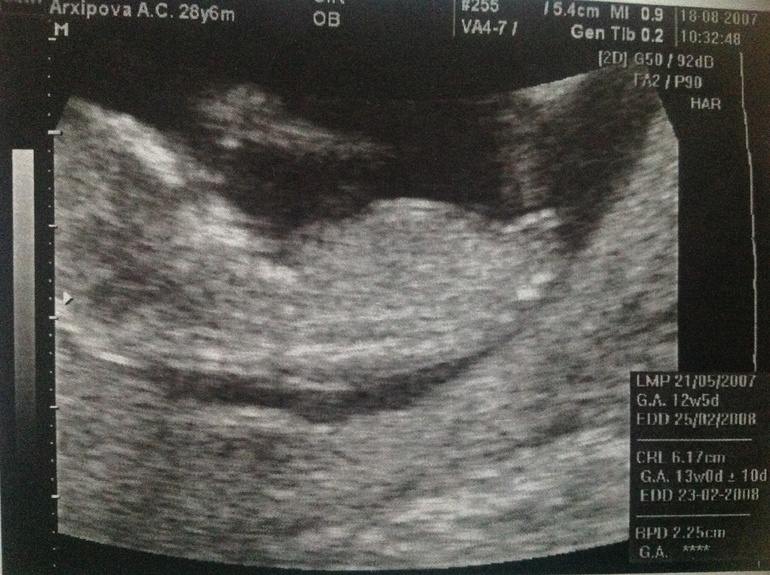

Полового бугорка не видно ни на одной фотке. Все, что виднеется это не оно. Вот смотрите у меня какие фотки тут видно отлично и это девочки обе.

О Нюша,спасибо за ваши фото,очень видно у вас,как показательные из инета)))

Ага это 3 и 4 дочи. Жду завтрашнее узи и посмотрим кто в домике живет

Да это 12.5 и 12.3. Завтра у меня как раз будет 12.3 тоже. По таким ракурсам я и сама определю кто там. Главное что бы были такие ракурсы и усе.